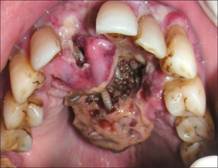

Thể bệnh dòi ở vết thương (Wound myiasis)

Thể bệnh dòi ở vết thương hở xảy ra khi ấu trùng ruồi nhiễm trùng vào vết thương hở. Nó là một biến chứng nghiêm trọng của các vết thương chiến tranh tại nhiều vùng nhiệt đới và đôi khi các vết thương này bị lãng quên ở một số nơi trên thế giới. Các yếu tố khiến dễ mắc bệnh gồm điều kiện kinh tế xã hội nghèo nàn, tuổi cao, rối toạn tâm thần, bệnh tâm thần kinh, nghiện rượu, tiểu đường và bệnh tim mạch, nhất là tắc nghẽn mạch.